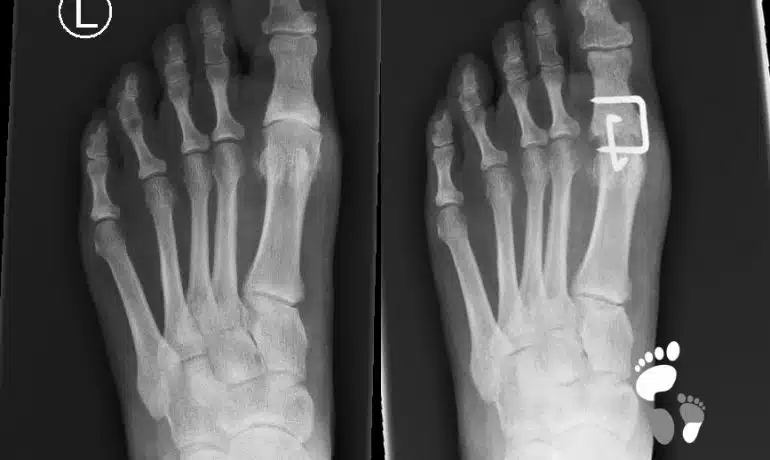

Arthrodese des Großzehengrundgelenks

Die Arthrodese des Großzehengrundgelenkes ist eine operative Methode zur Behandlung des endgradigen Hallux rigidus bzw. der Großzehengrundgelenks-Arthrose. Sie wird auch in der Hallux valgus-Chirurgie bei...